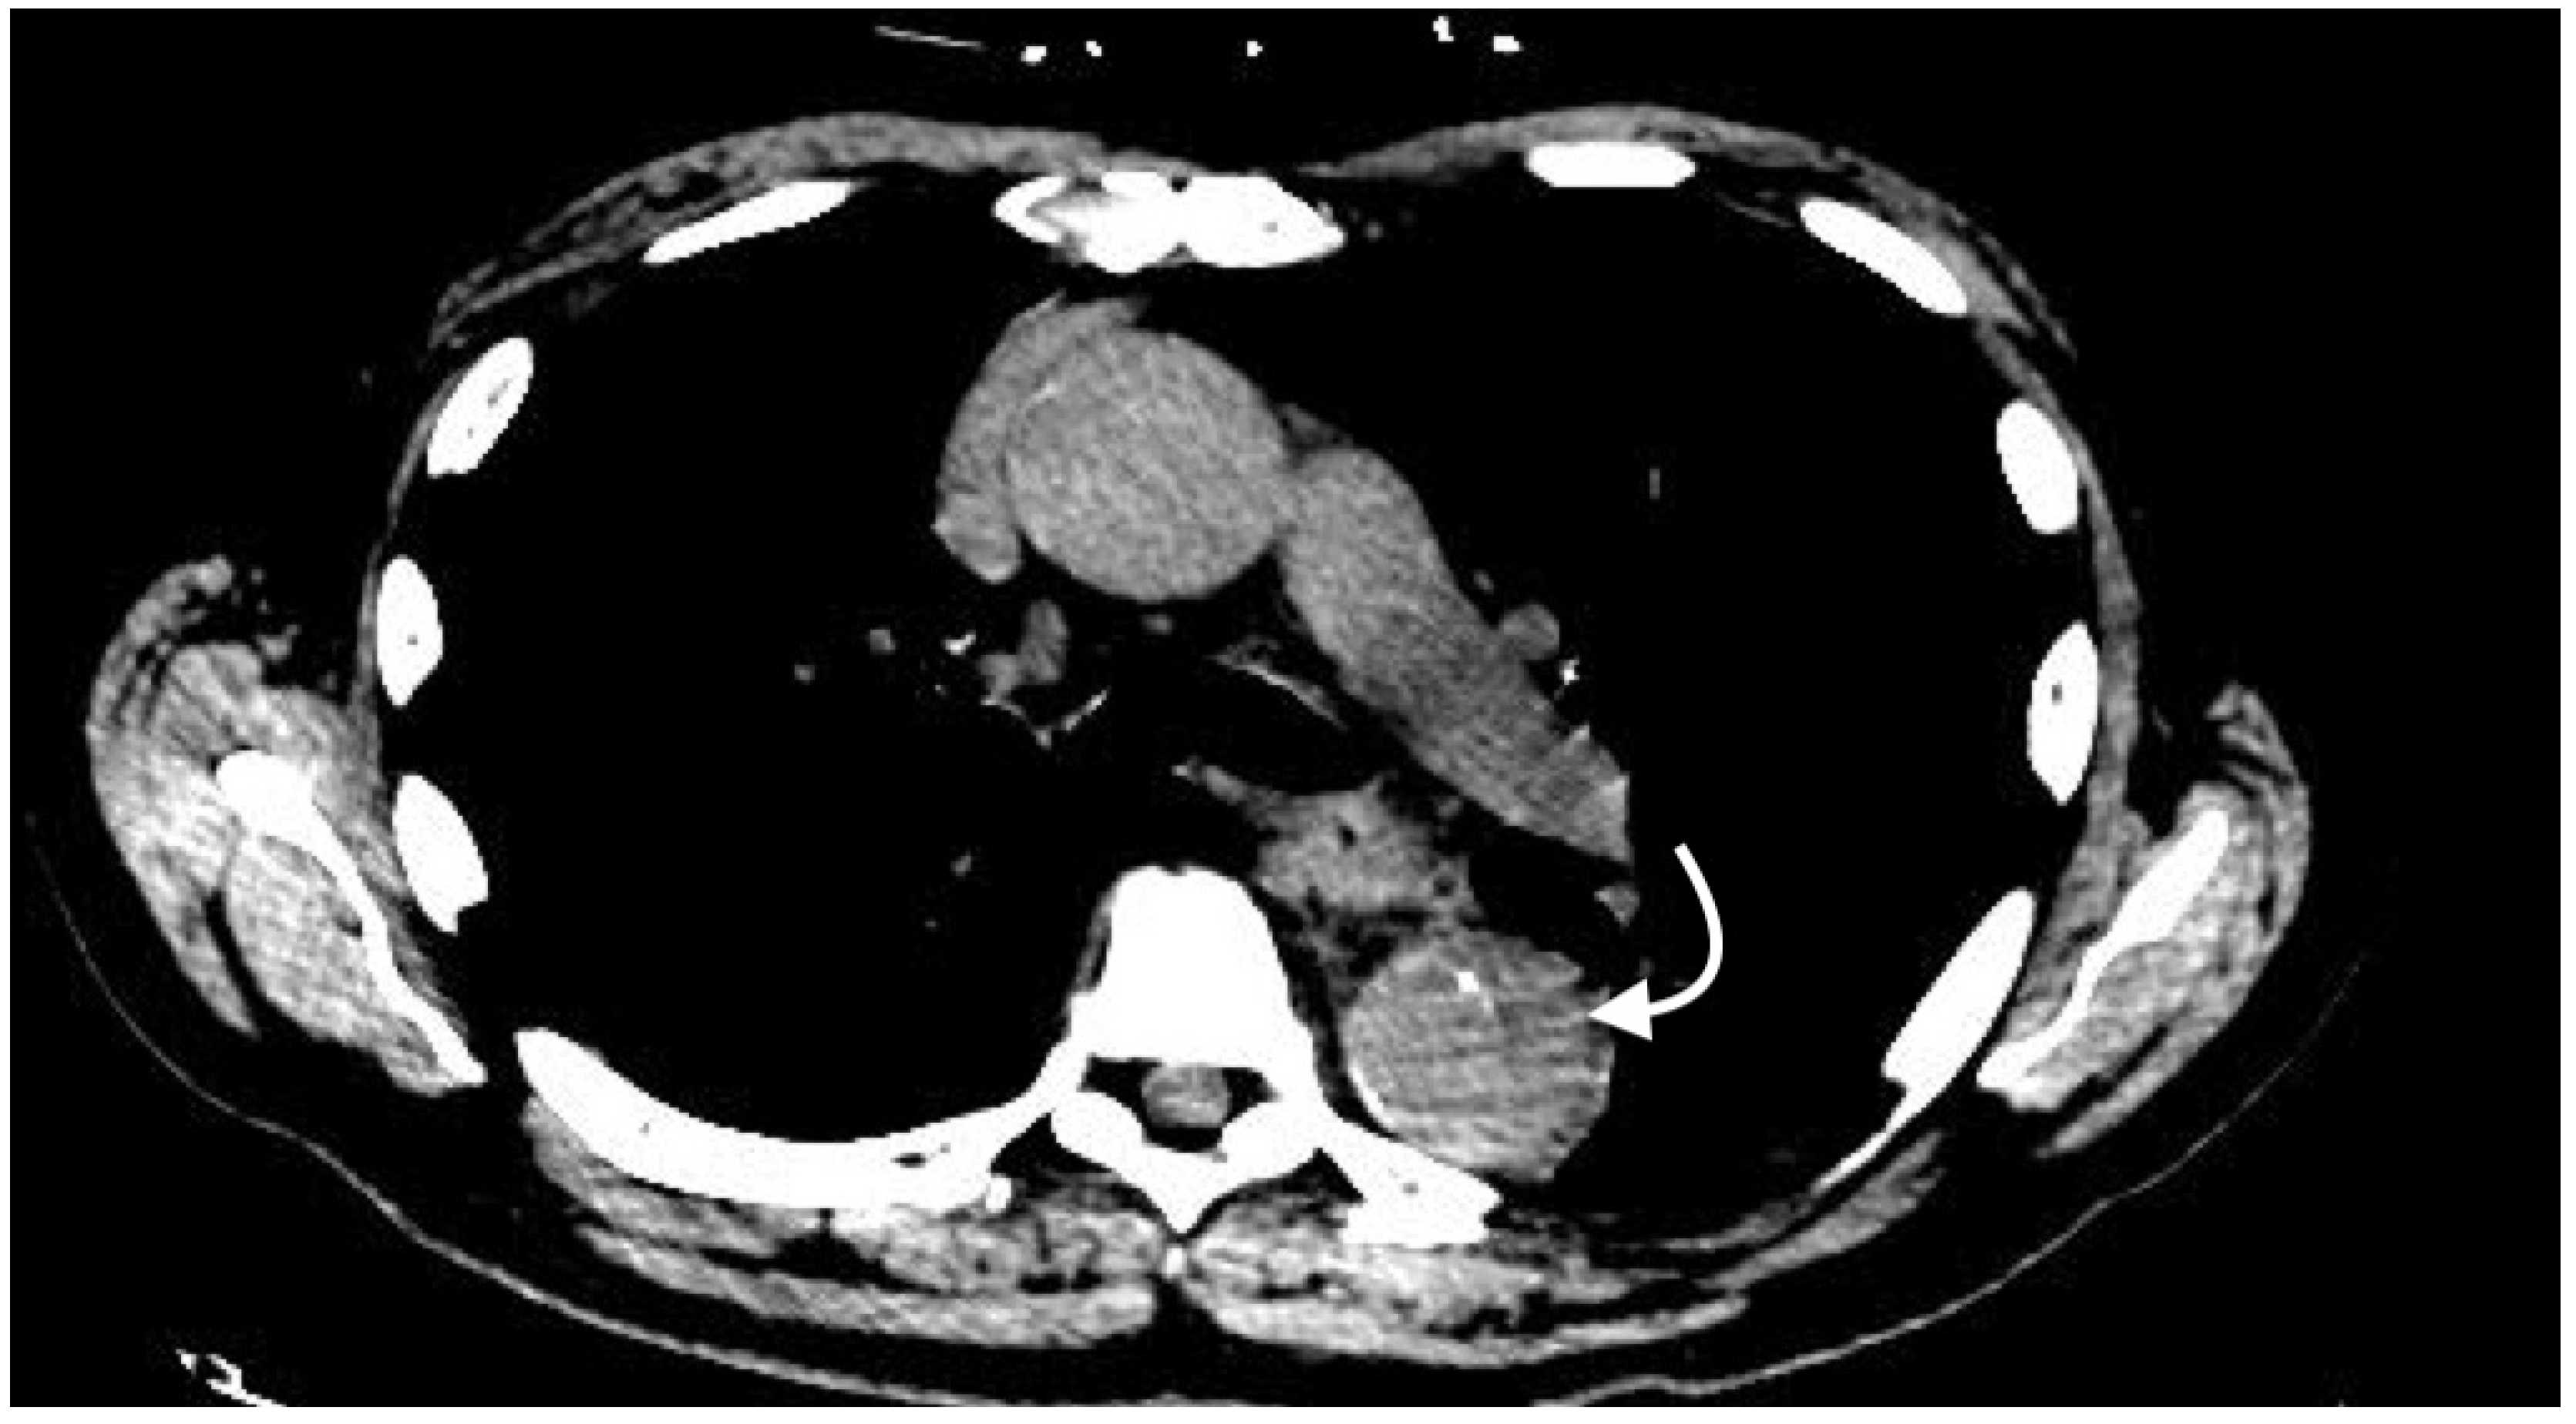

2.4.6. Arteriovenous Fistula